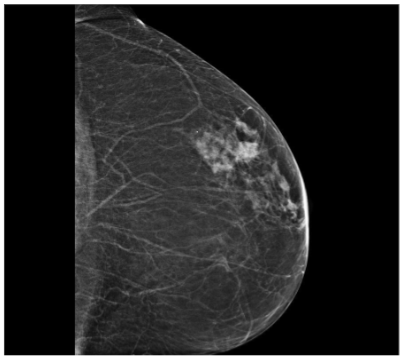

In September 2019, a 69-year-old woman presented to the emergency department of the University Hospital Città della Salute e della Scienza – Turin (Italy), reporting extreme fatigue and dyspnea. She had no comorbidities except for a medical history of papillary thyroid cancer, treated with thyroidectomy and radiotherapy 13 years before. Her complete blood count revealed anemia, thrombocytopenia and leukocytosis (Hb: 7.8 g/dL, PLT: 37 × 109/L, WBC: 45 × 109/L), while her physical examination was normal. The bone marrow smear showed 84% of blasts with myeloid immunophenotype (CD45, CD13, CD33, HLA-DR, lysozyme, CD36, CD64, CD11bc, partial CD14, and CD4 positive), molecular biology showed NPM1 mutation and FLT3-ITD positivity, while karyotype was normal (46, XX, 20/20). Consequently, a diagnosis of FLT3-ITD+ and NPM1 mutated t-AML was made. Induction chemotherapy was started with CPX-351 (liposomal daunorubicin 44 mg/m2 and cytarabine 100 mg/m2), obtaining CR with a 3-log NPM1 reduction (0.177). She was consolidated with CPX-351 (liposomal daunorubicin 29 mg/m2 and cytarabine 65 mg/m2 day 1 and 3), remaining in CR with persistent low level of measurable residual disease (MRD), NPM1 0.34. Meanwhile, we found a suitable HLA matched donor, but the patient refused the transplant procedure. Thus, we decided to start off-label azacitidine as maintenance therapy (50 mg/m2 subcutaneous daily for 5 days, every 28 days). Maintenance therapy was globally well tolerated, and the patient experienced only positivity for COVID-19 without need of hospitalization or additional care. She remained in CR with persistent MRD in BM (NPM1 0.044 after 12 cycles). During the fifteen course (May 2021), we found a palpable right mammary nodule on physical examination, confirmed on ultrasound, with a diameter of 18 x 11 mm. We stopped azacitidine and we promptly biopsied the nodule with a diagnosis of breast infiltration by AML blasts carrying the NPM1 mutation. CT scan and PET of chest, neck and abdomen were negative, and BM evaluation showed 1% blasts, with NPM1 0.044. The FLT3-ITD mutation resulted positive on breast cells while negative on medullary blasts. Thus, concluding for extramedullary relapse of AML FLT3-ITD mutated, we decided to start gilteritinib as single agent, at a dose of 120 mg daily. After 30 days, mammary ultrasound showed a reduction in diameter of the nodule, and in 4 months, the lesion has completely disappeared. The PET scan performed after 5 months of treatment was persistently negative and confirmed the absence of other uptakes. BM re-evaluation showed no blasts, with NPM1 0.006. Today, after 44 months of treatment, our patient is still in CR without signs of clinical and radiologic relapse. We continue monitoring her MRD status every two months on peripheral blood, as shown in table 1. Globally, therapy has been always well tolerated. In January 2024, we had to stop gilteritinib for 28 days due to pyelonephritis and sepsis treated with broad spectrum antibiotics. During this time, she remained in complete remission without any sign of relapse. After some months, in September, our patient has undergone exeresis of basal cell carcinoma, without complications and without need of stopping gilteritinib.

Myeloid sarcoma (MS), also referred to as extramedullary myeloid infiltration, was first described in 1811 by Burns. Initially, the tumor was called “chloroma” because of its greenish hue, which was later linked to the presence of the MPO (myeloperoxidase) enzyme by King in 1853. The tumor was identified as a mass composed of myeloid blasts, causing disruption in the normal tissue structure. The connection between MS and myeloid leukemia was first established in 1893 by Dock. Histologically, MS consists of immature granulocyte precursors, such as myeloblasts, promyelocytes, myelocytes, and granulocytes. Core biopsy is preferred over fine needle aspiration for the histologic and immunophenotypic evaluation, FISH, PCR and NGS allows a better understanding of the patient’s prognosis and identification of potential treatment targets. It is observed in 3-8% of adult patients with acute myeloid leukemia. It can occur in the context of intramedullary AML (synchronous extramedullary AML), or in an isolated form with an essentially normal bone marrow (isolated extramedullary AML; also called “nonleukemic” or “aleukemic”), which is usually followed by the development of metachronous intramedullary AML. Its frequency is higher in the post-allo-HSCT relapse setting with about 15% of all post allo-HSCT AML relapses being isolated EMI. While the exact cause of MS development remains unclear, it is thought to involve the migration of leukemia blasts to extramedullary sites, facilitated by specific adhesion molecules found on the blast cell surfaces. Age might influence the presence of MS; most studies have reported a median age at diagnosis ranging from 46 to 59 years, with approximately 52–59% of affected patients being male. Certain genetic features, including trisomy 8, monocytoid differentiation of blasts, MLL rearrangements, as well as CD56 positivity and the absence of CD117 (c-kit), are associated with an increased risk of developing MS in AML. These factors enhance the ability of leukemic cells to migrate to areas beyond the bone marrow. Recent reports have highlighted the frequent occurrence of FLT3 mutations in patients with EMI. FLT3-ITD mutations were the first molecular abnormalities to be identified in MS cells with initial studies detecting the mutation in up to about 30%, which is similar to the frequency noted for typical AML. NPM1 mutations are detected in up to 50% of cases, again comparable to conventional AML. MS in the breast is extremely rare, making up only about 3% of all MS cases, according to a Mayo Clinic study. Due to its infrequency, it is often mistaken for other breast malignancies, such as lobular carcinoma, non-Hodgkin’s lymphoma, or small round blue cell tumors. A recent review by Sharma et al. examined 67 previously reported cases, 66 of which were women and only one was a man. In most instances, breast MS presents as a rapidly enlarging mass, which may affect one or both breasts. Nipple retraction is generally not observed. Right-sided breast involvement is more common than left-sided. In terms of imaging, MS in the breast typically appears as a large, irregular, non-calcified mass with poorly defined, “feathery” margins, a characteristic finding consistent with the mammograms of the patients in the study. FDG-PET/CT at diagnosis, after treatment completion and at the time of suspected relapse is an important tool that allows for timely adjustments to the management strategy.